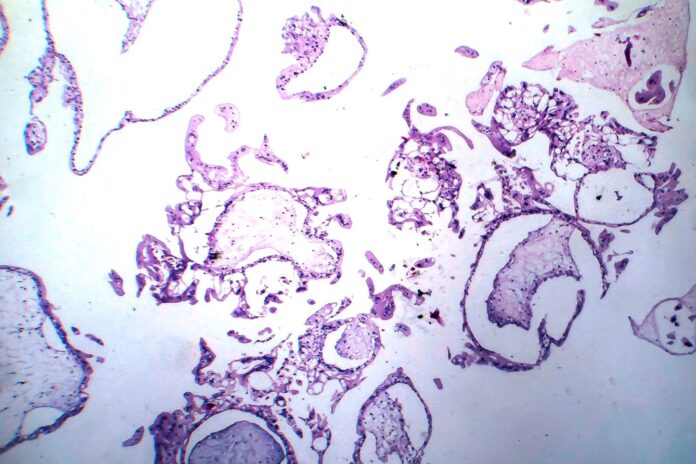

Zaśniad groniasty (w klasyfikacji ICD-10 oznaczony kodem O01) to niezłośliwy nowotwór łożyska, w którym dochodzi do nadmiernego rozrostu trofoblastu – zewnętrznej warstwy komórek otaczającej wczesny zarodek, odpowiadającej za jego zagnieżdżenie w macicy i tworzący część łożyska. W wyniku błędu podczas zapłodnienia dochodzi do obrzęku kosmków łożyska, które tworzą przypominające winogrona (groniaste) struktury.

Zaśniad groniasty całkowity powstaje, gdy pusta komórka jajowa (pozbawiona materiału genetycznego matki) zostaje zapłodniona przez jeden plemnik, który następnie duplikuje swoje DNA, lub przez dwa plemniki. W wyniku tego rozwija się diploidalny materiał genetyczny pochodzący wyłącznie od ojca, zazwyczaj o zestawie chromosomów 46,XX, rzadziej 46,XY. Nie tworzy się zarodek, a w jamie macicy obecne są obrzęknięte kosmki łożyskowe.

W obrazie USG brak jest płodu oraz płynu owodniowego, zamiast nich widoczny jest charakterystyczny obraz „burzy śnieżnej”, będącej efektem chaotycznego rozrostu trofoblastu. Typowe jest także znacznie podwyższone stężenie gonadotropiny kosmówkowej (beta-hCG), często kilkakrotnie wyższe niż w prawidłowej ciąży na tym etapie.

Zaśniad groniasty częściowy rozwija się, gdy prawidłowa komórka jajowa zostaje zapłodniona przez dwa plemniki, co prowadzi do powstania nieprawidłowego, triploidalnego materiału genetycznego, najczęściej 69,XXY, rzadziej 69,XXX lub 69,XYY.

W zaśniadzie częściowym może rozwinąć się zarodek, jednak jest on zwykle ciężko uszkodzony i niezdolny do rozwoju. W USG często widoczny jest płód z cechami obrzęku, wady rozwojowe lub pęcherzykowate zmiany w obrębie łożyska. Stężenie beta-hCG bywa podwyższone, ale zwykle nie tak znacznie jak w przypadku zaśniadu całkowitego.

- badanie ultrasonograficzne (USG przezpochwowe i przezbrzuszne): w zaśniadzie całkowitym typowy jest obraz „burzy śnieżnej”, natomiast w częściowym niekiedy możliwe jest uwidocznienie płodu oraz nieprawidłowo zmienionego łożyska,

- badanie histopatologiczne materiału po łyżeczkowaniu macicy: potwierdza ostateczne rozpoznanie.